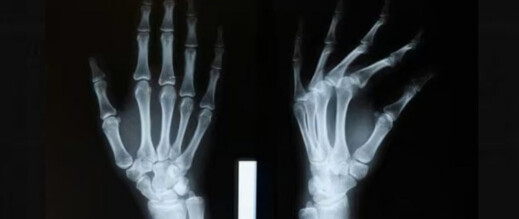

أعلن علماء صينيون عن تطوير غراء لاصق لعلاج كسور العظام، قادر على إصلاح الشظايا المكسورة والمهشمة في غضون ثلاث دقائق فقط.

وكشف فريق بحثي في مقاطعة تشجيانغ شرق الصين عن هذا الغراء، الذي أطلق عليه اسم “بون 02”، الأسبوع قبل الماضي، وفق تقرير صحيفة غلوبال تايمز الصينية.

وقال لين شيانفينغ، رئيس قسم جراحة العظام بمستشفى سير ران ران شو: إن فكرة تطوير الغراء جاءت من ملاحظة محار يتشبث بقوة بجسر تحت الماء، مشيراً إلى أن المادة اللاصقة قادرة على إصلاح الكسور خلال دقيقتين إلى ثلاث دقائق، حتى في الحالات التي تكون فيها الإصابة غنية بالدم.

ويعد هذا الابتكار خطوة نوعية في علاج كسور العظام، لما يوفره من تثبيت سريع وفعال يقلل الحاجة إلى العمليات الجراحية التقليدية.